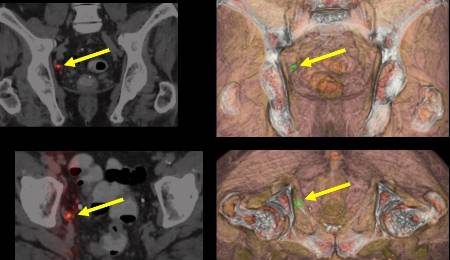

Tal y como explica el doctor Antonio Maldonado, Jefe de Medicina Nuclear e Imagen Molecular del Hospital Universitario La Luz de Madrid, aunque clásicamente se ha usado la imagen anatómica CT y funcional de la gammagrafía ósea en el cáncer de próstata, ambas han sido claramente superadas por las dos exploraciones de imagen molecular avanzada como son el PET-CT (fundamentalmente con PSMA) y la RM multiparamétrica. "La información aportada por ambas pruebas convierte a la PET-RM en pieza indispensable en todo lo que se refiere al manejo de estos pacientes", asevera el doctor.

Como indica este experto en la introducción de la imagen PET en España, en el diagnóstico inicial, la biopsia fusión con RM se ha convertido en habitual en nuestro medio hospitalario por las ventajas tanto diagnósticas como de seguridad para el paciente en la toma de muestras. "La introducción de la imagen PET-CT PSMA a este dúo diagnóstico, permite aún más, mejorar en la correcta selección de las áreas con tumor dentro de la glándula prostática", asevera Maldonado.

De acuerdo al doctor Antonio Maldonado, el PET-CT PSMA completa el escenario al ser la técnica que mejor permite detectar metástasis a distancia. "Desde el punto de vista oncológico, la valiosa información TNM molecular no está orientada tanto al tipo de tratamiento a aplicar sino a ser una fuente importante de información de pronóstico y supervivencia de la enfermedad", resalta el experto.

Según el doctor Maldonado, en la detección de enfermedad tumoral ante recidiva bioquímica es donde la imagen molecular avanzada PET-CT con radiofármacos PSMA (18F o 68Galio) supera al resto de pruebas de imagen. "Su información es clave para la toma precoz de decisiones de tratamiento, mejorando de esta forma espectacularmente el control de la enfermedad", matiza.